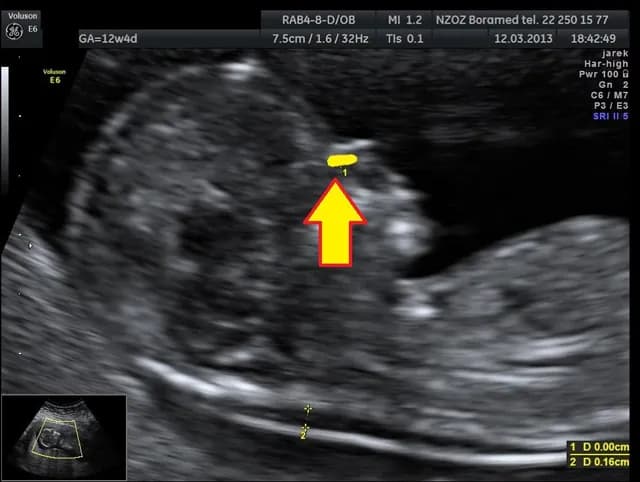

Czy na USG można wykryć zespół Downa? Dowiedz się, jakie cechy mogą wskazywać na ryzyko i jakie badania warto rozważyć w ciąży.